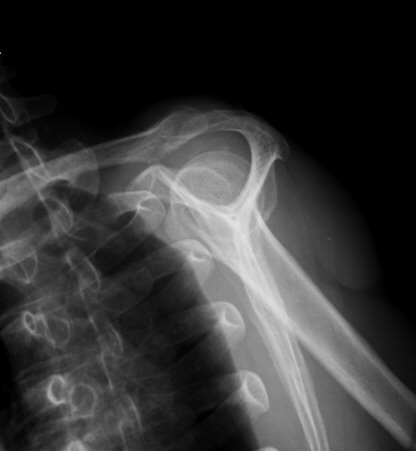

´Ü¼ø¹æ»ç¼±°Ë»ç

¼®È¸È­ À½¿µÀÌ °üÂû µÊ(±×¸² 9, 10)